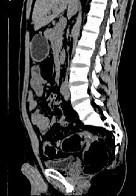

问题 女,51岁,腹胀、腹痛、进行性消瘦,影像检查如下图,最佳诊断是 ( )

选项 A.乙状结肠Crohn病 B.乙状结肠结核 C.乙状结肠癌 D.乙状结肠淋巴瘤 E.乙状结肠息肉

答案 C